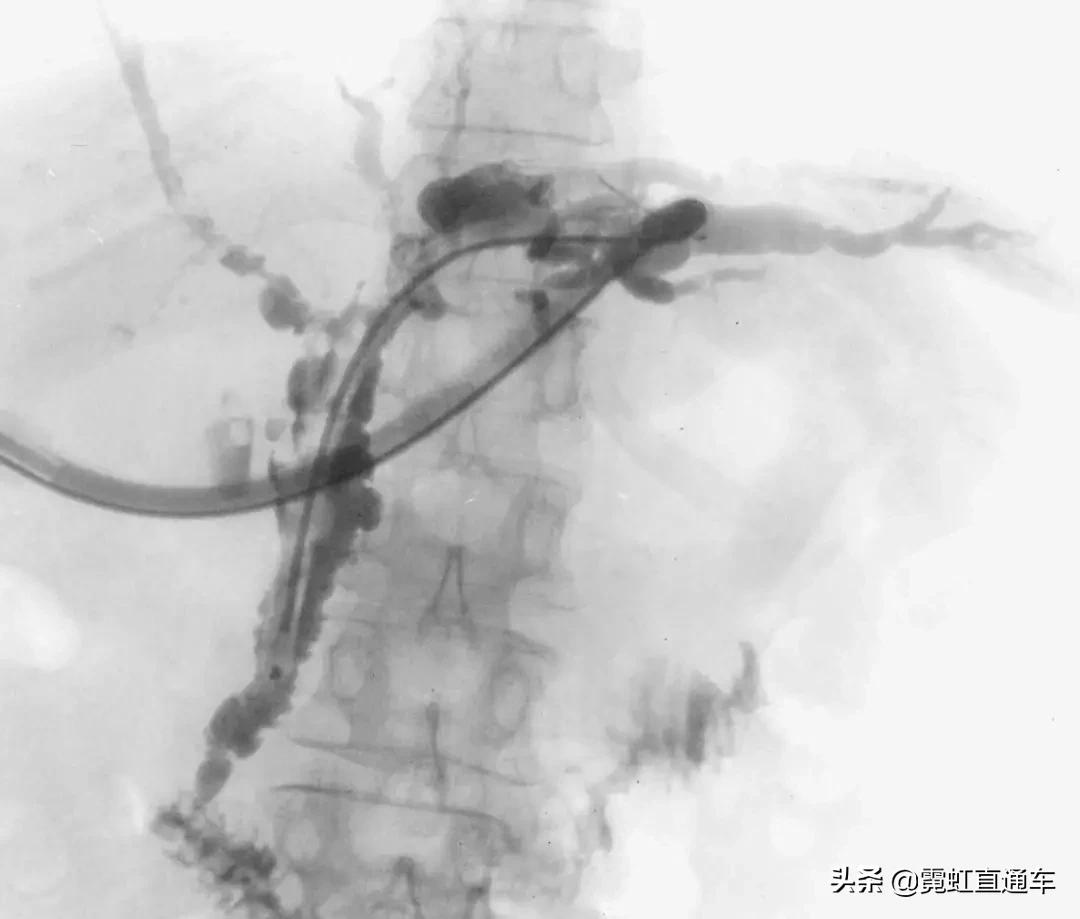

3、PSC影像学表现(日本厚生劳动省官网提供)

ERCP:胆管狭窄与扩张交互,呈串珠状改变

多发短小狭窄,胆管环状受累

PTCD:胆管呈边缘不整羽毛状

ERC:胆管壁呈憩室样突出